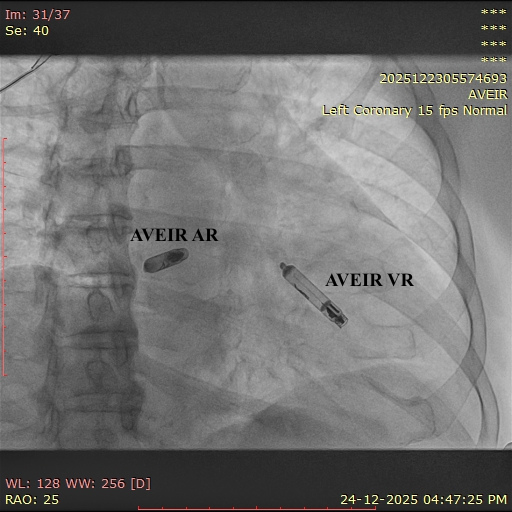

The Abbott AVEIR™ DR is the world’s first dual-chamber leadless pacemaker designed to treat abnormal heart rhythms using two miniature devices implanted directly inside the heart — one in the right atrium and one in the right ventricle. Unlike traditional pacemakers, this innovative system works without wires, chest pockets, or surgical incisions.

The system includes two small catheter-delivered devices:

AVEIR AR – placed in the right atrium

AVEIR VR – placed in the right ventricle

Using advanced implant-to-implant (i2i) wireless communication, both devices coordinate on a beat-to-beat basis to maintain natural heart rhythm and support dual-chamber pacing modes.